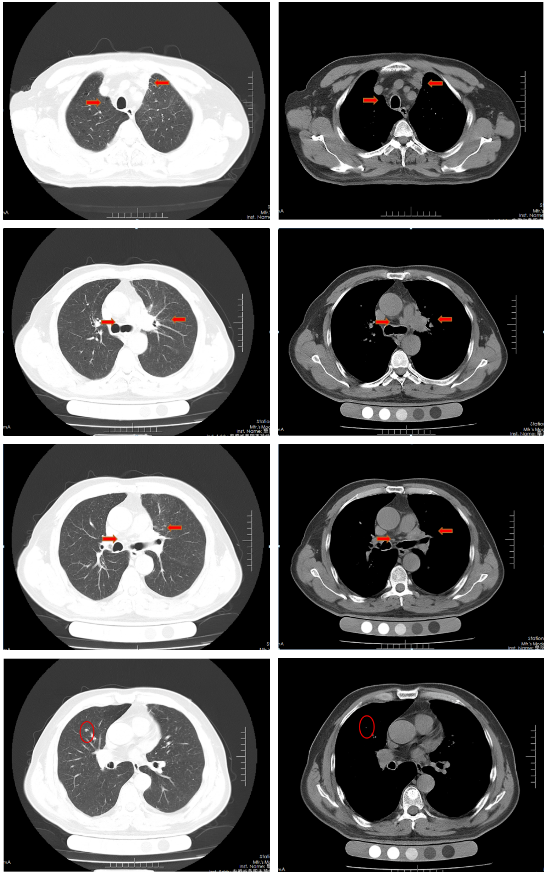

胸部增强CT(2022-02-12):左肺门及纵隔内见团块状软组织密度影,大小约62mm×42mm,边界不规整,内见血管影穿行,增强扫描呈轻度强化,局部支气管狭窄,远端肺内见片状磨玻璃密度影,边界欠清。右肺上叶见结节状密度增高影,较大直径约为8mm,增强扫描呈轻中度强化,右侧斜裂见长径约为6mm的高密度影,增强扫描未见明显强化;两肺透亮度增强,左肺下叶胸膜下囊状透光区。余气管、支气管通畅,未见明显狭窄、阻塞。纵隔和左肺门区见多发肿大淋巴结影,部分融合。两侧胸腔无明显积液。胸部CT诊断:左肺门及纵隔内占位,考虑肺Ca;纵隔及左肺门淋巴结肿大;右肺上叶结节,转移可能;右侧斜裂下结节;两肺肺气肿、左肺下叶肺大泡。

胸部CT(2022-04-12):左肺门及纵隔内见团块状软组织密度影,大小约57mm×37mm,边界不规整,局部支气管狭窄,远端肺内见片状磨玻璃密度影,边界欠清。右肺上叶见结节状密度增高影,较大直径约为9mm,右侧斜裂见长径约为7mm的高密度影;两肺透亮度增强,左肺下叶胸膜下囊状透光区;两肺可见索条状影。余气管、支气管通畅,未见明显狭窄、阻塞。纵隔和左肺门区见多发肿大淋巴结影,部分融合。两侧胸腔无明显积液。胸部CT诊断:左肺占位复查;纵隔及左肺门淋巴结肿大;右肺上叶结节,转移可能;右侧斜裂下结节;两肺肺气肿、左肺下叶肺大泡。

治疗后评价:经过EP方案治疗后两周期,患者仍有咳嗽、咳痰及左侧胸痛,症状无缓解,且出现体重下降;影像学检查提示左肺病灶及纵膈淋巴结及肺门淋巴结较前缩小不明显(缩小<30%),疗效评价SD。总体效果欠佳。

胸部CT(2022-07-15):双侧肺野透亮度增加,以两上肺和胸膜下明显。双肺纹理增多、增粗,紊乱,左肺上叶条片状高密度灶,大小约45mm×19mm,小叶间隔增厚。气管、左右主支气管无明显狭窄。纵隔内未见肿大淋巴结影。两侧胸腔无明显积液。胸部CT诊断:左上肺门占位复查;慢性支气管炎-肺气肿样改变。

治疗后评价:患者经过EP方案联合斯鲁利单抗治疗四周期后,患者咳嗽、咳痰及左侧胸痛症状消失,体重逐渐恢复;影像学提示左肺病灶及纵膈淋巴结及肺门淋巴结较前明显缩小(缩小>30%),右肺结节基本消失;疗效评价:PR(接近CR)。

胸部CT(2022-08-30):双侧肺野透亮度增加,以两上肺和胸膜下明显。双肺纹理增多、增粗,紊乱,左肺上叶见条片状高密度灶,大小29mm×18mm,小叶间隔增厚,两肺下叶见囊状透亮区。气管、左右主支气管无明显狭窄。纵隔内未见肿大淋巴结影。两侧胸腔无明显积液。胸部CT诊断:左上肺门占位复查;慢性支气管炎-肺气肿样改变;两肺下叶肺气肿。

治疗后评价:患者经过斯鲁利单抗单药维持治疗两周期后,患者未再出现咳嗽等症状,体重逐渐增加。影像学提示左肺病灶及纵隔淋巴结及肺门淋巴结、右肺结节基本消失,疗效评价接近CR。

病例小结

该患者为ⅣB期小细胞肺癌,一线采用标准化疗方案(EP)治疗2周期后疗效评估:SD,患者化疗敏感性不高;第二阶段治疗根据2022年CSCO小细胞肺癌诊疗指南,患者采用斯鲁利单抗联合EP方案,治疗2周期后体力状况明显改善,4周期后疗效评估:PR;第三阶段采用斯鲁利单抗单药维持治疗,2周期后影像学评估,左肺病灶及纵膈淋巴结及肺门淋巴结、右肺结节基本消失,疗效评估:接近CR。